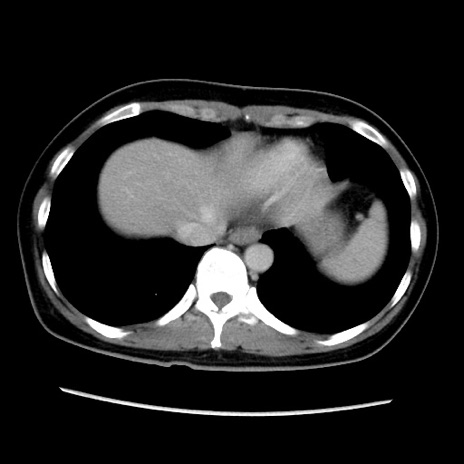

症例39(横断像)

【症例】40歳代女性

【主訴】上下腹部痛

【現病歴】2日目から下腹部痛あり。夜間は痛みで眠れなかった。昨日より上腹部痛と下痢が出現。臥位で痛みは軽快したため、休んでいた。本日になって臥位でも立位でも痛みが強くなってきたため救急要請。

【既往歴】子宮内膜症

【身体所見】部:平坦・軟、左上下腹部に圧痛あり、反跳痛あり。

【データ】WBC 21800、CRP 26.78